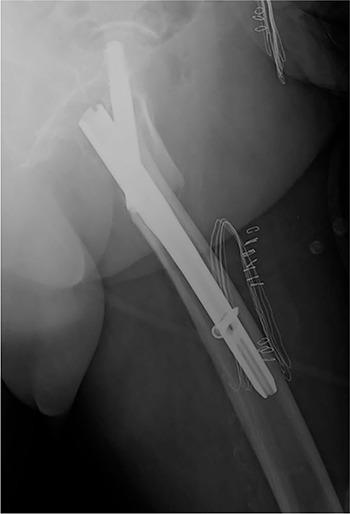

Pertrochanteric hip fractures are among the most common and the use of short cephalomedullary nails as the treatment of choice is increasing.A systematic review regarding distal locking options for short cephalomedullary nails was undertaken using Medline/PubMed®, Embase® and Cochrane Library® in order to evaluate current indications, associated complications and to provide treatment recommendations.The results seem to support the use of distal static locking for unstable fractures, dynamic locking for length stable/rotational unstable fractures and no locking for stable fractures.Complications associated with distal locking include iatrogenic fractures, thigh pain, delayed union and nonunion, implant failure, screw loosening and breaking, drill bit breaking, soft tissue irritation, femoral artery branch injury, intramuscular haematoma and compartment syndrome. It is also associated with longer operative time and radiation exposure.In unlocked constructs, dorsomedial comminution and nail/medullary canal mismatch contribute to peri-implant fractures. Anterior cortical impingement is associated with cut-out and nonunion.Most studies comparing distally locked and unlocked nails report a short follow-up.Distal locking mode should be based on the fracture's stability. Cite this article: 2020;5:421-429. DOI: 10.1302/2058-5241.5.190045.

转子周围髋部骨折是最常见的骨折之一,使用短髓内钉作为首选治疗方法的情况正在增加。我们使用Medline/PubMed®、Embase®和Cochrane图书馆®对短髓内钉的远端锁定选择进行了系统评价,以评估当前的适应证、相关并发症并提供治疗建议。结果似乎支持对不稳定骨折采用远端静态锁定,对长度稳定/旋转不稳定骨折采用动态锁定,对稳定骨折不进行锁定。与远端锁定相关的并发症包括医源性骨折、大腿疼痛、延迟愈合和不愈合、植入物失败、螺钉松动和断裂、钻头断裂、软组织刺激、股动脉分支损伤、肌内血肿和骨筋膜室综合征。它还与更长的手术时间和辐射暴露有关。在非锁定结构中,背内侧粉碎和钉/髓腔不匹配会导致植入物周围骨折。前皮质撞击与穿出和不愈合有关。大多数比较远端锁定和非锁定髓内钉的研究报告的随访时间较短。远端锁定方式应基于骨折的稳定性。引用本文:2020;5:421 - 429。DOI:10.1302/2058 - 5241.5.190045。